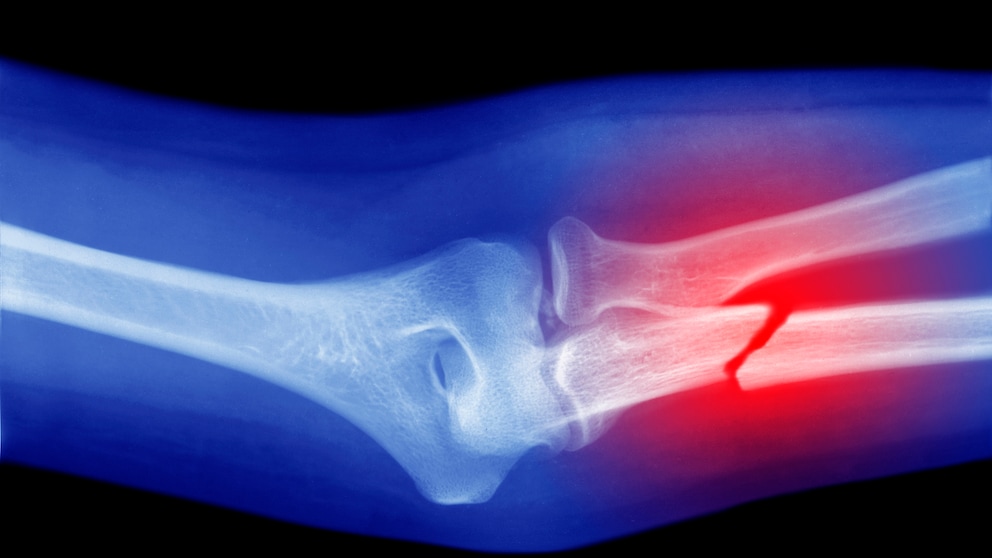

Frailty refers to a generally increased vulnerability of older people to stress factors such as overexertion and illnesses. Due to the physiological aging process, resistance to stressors decreases, leading to slower healing and recovery processes after injuries and illnesses. But when does frailty begin? And can it be precisely determined? Canadian researchers provide an answer in a recent study. According to them, the tipping point for frailty occurs around the age of 75. At this age, the body can no longer recover as easily from injuries and illnesses, as reported by researchers from Dalhousie University. This is accompanied by an increased risk of death.